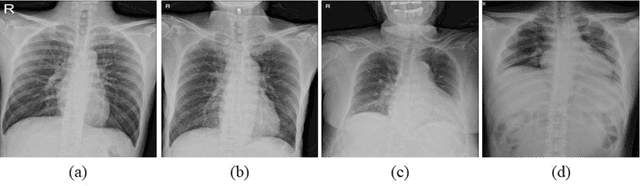

Purpose. Imaging plays an important role in assessing severity of COVID 19 pneumonia. However, semantic interpretation of chest radiography (CXR) findings does not include quantitative description of radiographic opacities. Most current AI assisted CXR image analysis framework do not quantify for regional variations of disease. To address these, we proposed a four region lung segmentation method to assist accurate quantification of COVID 19 pneumonia. Methods. A segmentation model to separate left and right lung is firstly applied, and then a carina and left hilum detection network is used, which are the clinical landmarks to separate the upper and lower lungs. To improve the segmentation performance of COVID 19 images, ensemble strategy incorporating five models is exploited. Using each region, we evaluated the clinical relevance of the proposed method with the Radiographic Assessment of the Quality of Lung Edema (RALE). Results. The proposed ensemble strategy showed dice score of 0.900, which is significantly higher than conventional methods (0.854 0.889). Mean intensities of segmented four regions indicate positive correlation to the extent and density scores of pulmonary opacities under the RALE framework. Conclusion. A deep learning based model in CXR can accurately segment and quantify regional distribution of pulmonary opacities in patients with COVID 19 pneumonia.